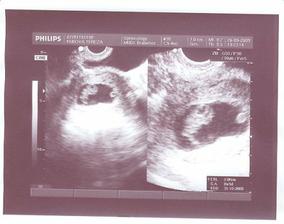

Od 3.9. máme klidový režim, nejlépe nic nedělat jen polehávat a šetřit se. Aby nám nehrozil předčasný porod, to by bylo opravdu moc brzy, pan doktor nás ještě hnal na monitor a to jsme byli 32+2, tak jsme jeli, monitor dopadl v pořádku. Nelíbí se mi snížené hrdlo, vysoké cervix score 4 a dráždivá děloha, máme s taťkou zakázané milování, ale to nevadí pro Honzíka všechno.Jinak Honík vážil 1827gramů.Další kontorla v 33+2, nic se nezměnilo až na CS 4-5.